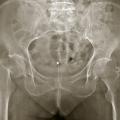

Si, à la lecture de la radiographie, il n’y a pas de fracture évidente au niveau de l’extrémité supérieure du fémur, il faut bien regarder au niveau des branches ilio- et ischiopubiennes, dont la fracture constitue le principal diagnostic différentiel clinique. Il faut également s’assurer qu’il n’y ait pas de fracture habituellement peu déplacée du cotyle. En l’absence de telle fracture avec néanmoins une symptomatologie caractéristique, il faut poursuivre les investigations. L’IRM serait a priori le meilleur examen, mais son accès n’est pas toujours facile en urgence, et un bon nombre de patients sont porteurs de pacemaker, qui contre-indique formellement cet examen. Il est donc réalisé en général un scanner, au mieux associé à une scintigraphie. C’est ce qui permet de faire le diagnostic des fractures occultes.

Les fractures pathologiques ne sont pas rares au niveau de l’extrémité supérieure du fémur. Il faut toujours analyser rigoureusement la trame osseuse, à la recherche d’ostéolyse ou d’image anormale. Il faut également rechercher de telles images sur le reste du fémur et sur le bassin, constituant alors un argument de plus en faveur d’une fracture sur métastase.